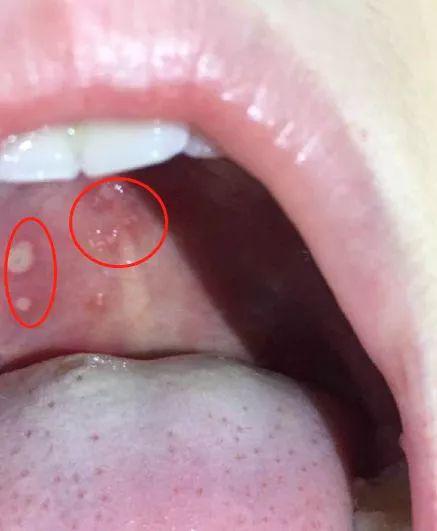

如果宝宝有双手低烧不退、小脚,小屁股和嘴巴里都长出泡疹,那十有八九就是手足口了。

像这样

左右滑动 看看详细的疾病